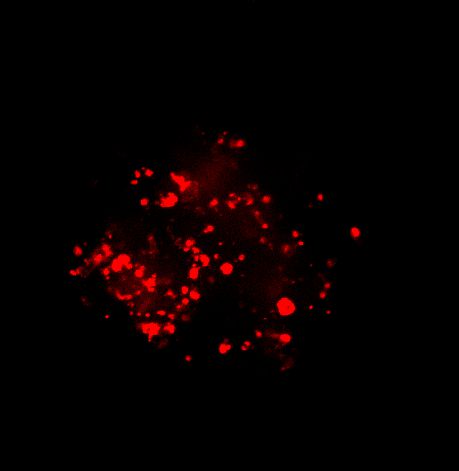

图 A:使用 20 倍空气物镜(顶部)和 25 倍硅油物镜(底部)获得的肿瘤球体 Z 堆栈的最大密度投影 (MIP)。活细胞用钙黄绿素(绿色)标记,死细胞用 PI(红色)标记。细胞核用 Hoechst(蓝色)染色。比例尺:100 um。这些图像是使用 CrestOptics X-Light V3 转盘获取的。

图 C:使用 20 倍空气物镜(左)和 25 倍硅油物镜(右)获得的球体的 3D 体积视图。活细胞用钙黄绿素(绿色)标记,死细胞用 PI(红色)标记。细胞核用 Hoechst(蓝色)染色。沿 Z 轴的比例尺:120 um。这些图像是使用 CrestOptics X-Light V3 转盘获取的。